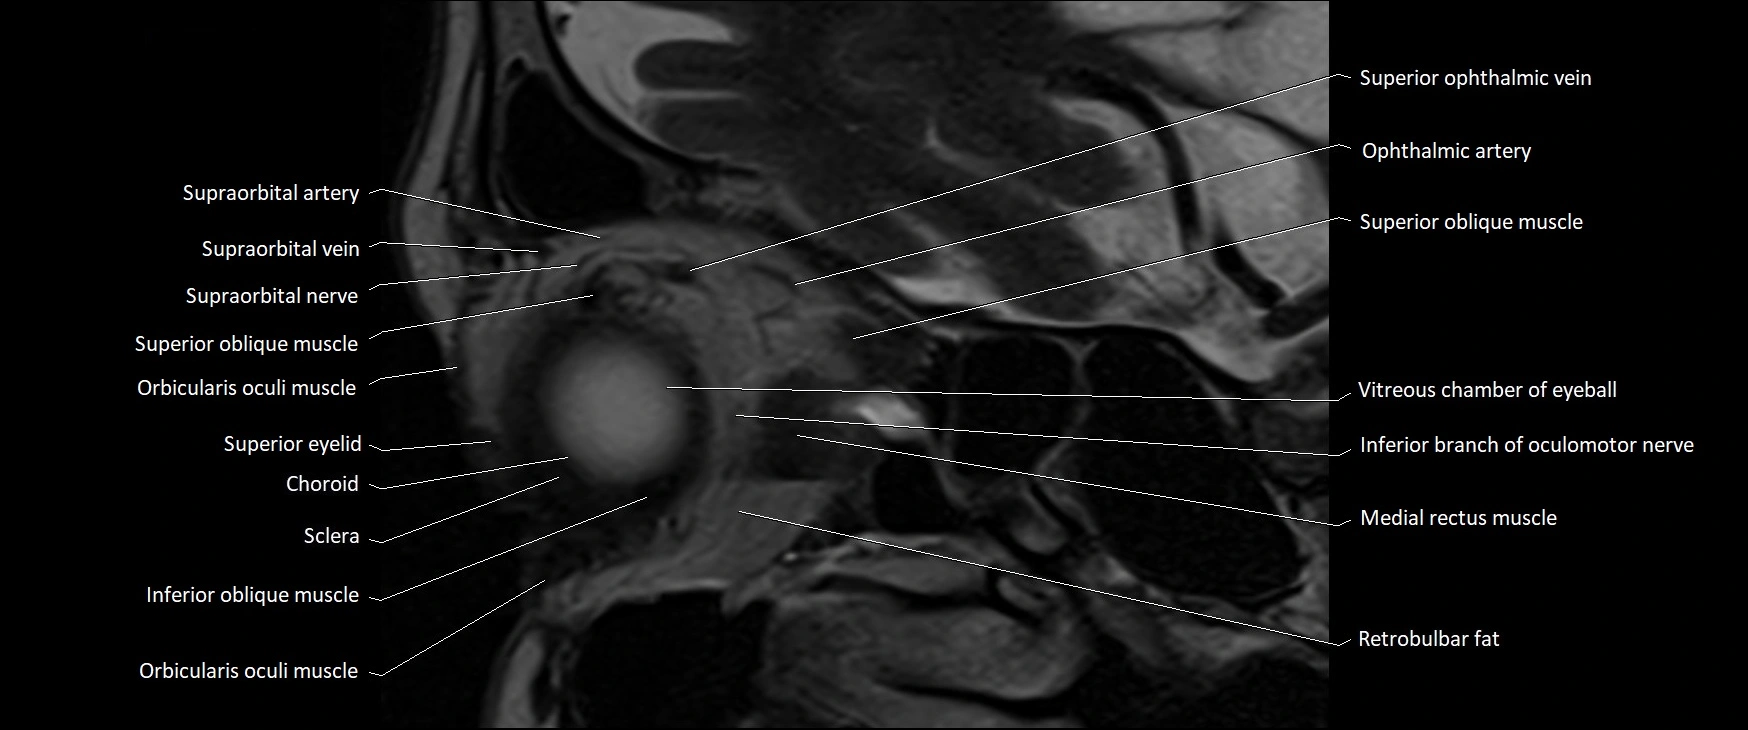

- Orbicularis oculi muscle

- Superior eyelid

- Sclera

- Choroid

- Inferior oblique muscle

- Medial rectus muscle

- Superior ophthalmic vein

- Retrobulbar fat

- Oculomotor nerve (inferior branch)

- Supraorbital artery

- Supraorbital nerve

- Supraorbital vein

- Superior oblique muscle

- Vitreous chamber of eyeball